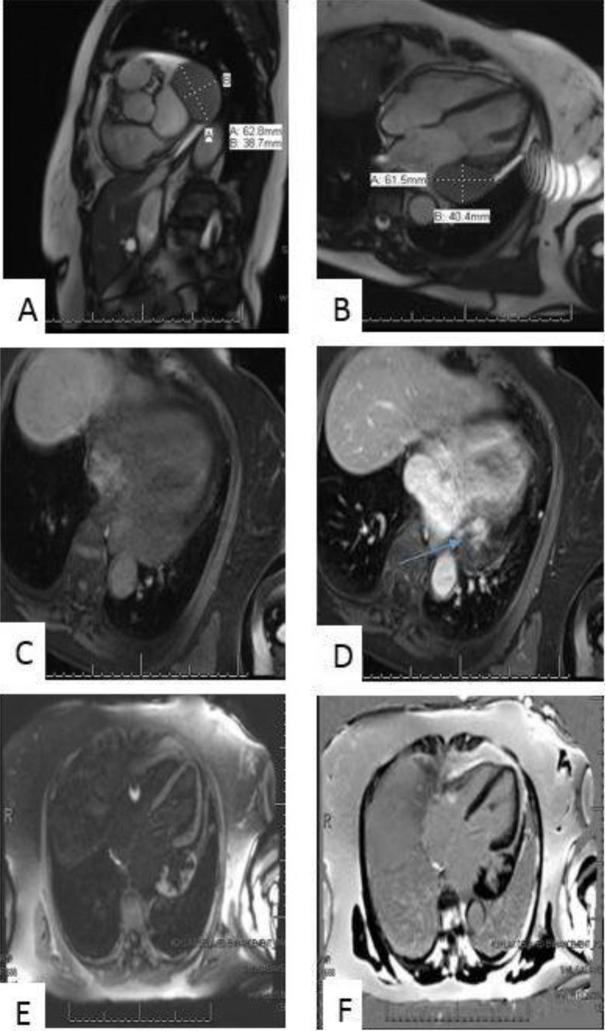

Epicardial Cavernous Hemangioma: A Diagnostic Challenge.

• Primary cardiac tumors, although rare, represent a wide differential diagnosis. • It is often difficult to decipher the type of tumor from imaging alone. • This case highlights imaging modalities to plan surgical removal of cardiac masses.

• 本病例重点介绍了用于规划心脏肿块手术切除的影像学检查方法。